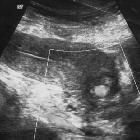

Ultrasound

Small focus of color signal on Doppler ultrasound with distinctive "to-and-fro" waveform at the neck of the pseudoaneurysm .